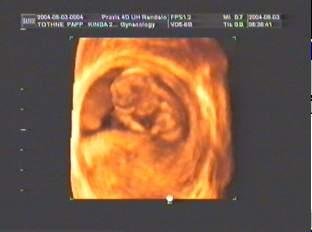

A pici szerintem még fel se fogta, de a két nagyobb aranyos volt. A legnagyobb minddenképpen be akart jönni UH-ra, de mondtam neki, még nem lehet (hüvelyi volt). A 12. hetit majd felvetetjük DVD-re és megnézheti itthon.

Én úgy tudom, ha kislányt mondanak UH-n, az biztosabb. A kisfiú csak akkor, ha tutira az látszik. Egy 4D UH-n sokkal biztosabbra meg tudják mondani (persze ott is csak akkor, ha nem takargatja).

Nem ciki, ha nem látod, mit kéne látnod. Kérj róla videó vagy DVD felvételt (mozgóképet). Nézd meg 50-szer és látni fogsz mindent. A 2. terhességnél meg már akár magadnak is csinálhatod

. (Én a másodiknál azt is megláttam, amit nem akartam. Egy pillanatra áthúzta a vizsgálófejet a doki azon a bizonyos részen (amit mi nem akartunk tudni) és itthon mégis felfedeztem

. Azóta nem is nézek UH-t, csak ha biztos nem nézi azt a részt, mert tuti meglátnám!:) (Jó, nem a 12 hetesen, de mondjuk a 28 hetesen már biztosan, ha nem takargatja magát.))